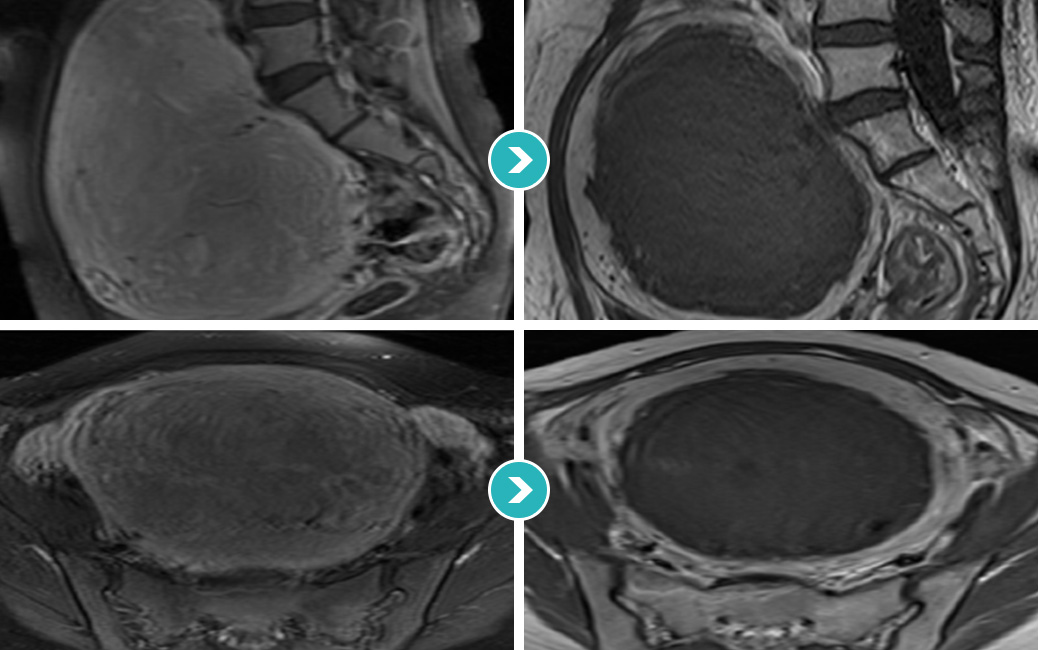

거대자궁근종(14Cm) 하이푸 치료18개월 장기간 추적관찰 STORY

2014년 5월 거대 자궁근종 하이푸 시술 후 95% 이상 괴사

2015년 5월 자궁근종 하이푸 치료후 18개월 MRI 사진상 자궁근종의 부피 80.31% 감소